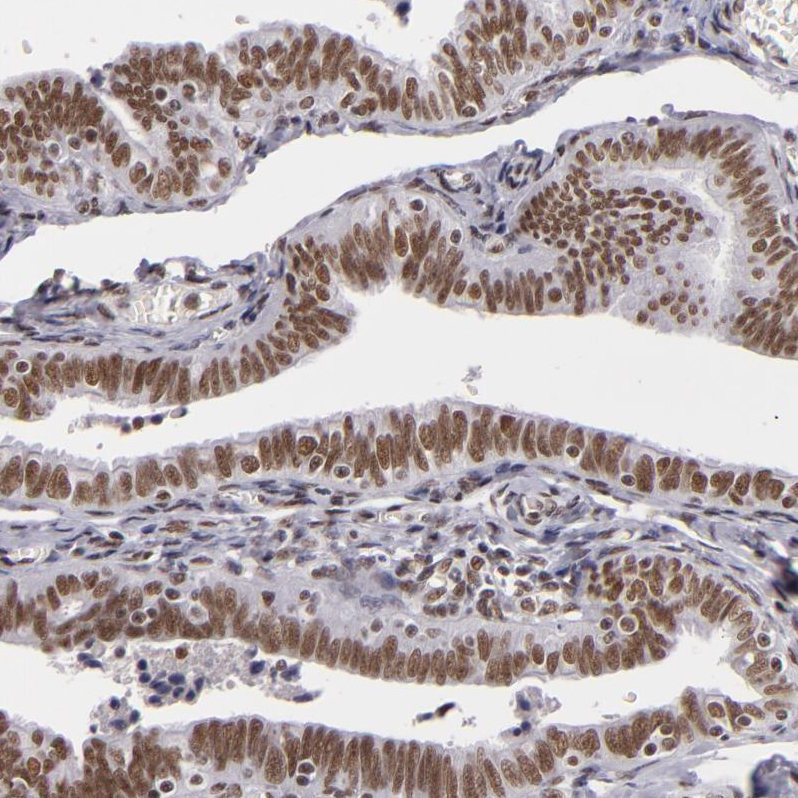

Immunohistochemical staining of human testis shows strong nuclear positivity in cells in seminiferous ducts.